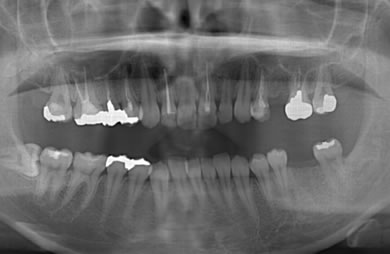

インプラントの症例写真 IMPLANT

骨再生インプラント治療+セラミック治療

| 治療方針 | 左側の奥歯の部分の歯が欠如しているのでインプラント治療にて機能的・審美的回復を行いつつ、その他の虫歯の部分はセラミック歯にて治療を行う。 | ||||||||||||||||||||||||||||||||

| 治療内容 | インプラント2本(ソケットリフト)、ハイブリッドセラミック2本、オールセラミック3本(オールセラミック用の土台3本)、メタルボンドセラミック2本(メタルボンドセラミック用の土台1本) | ||||||||||||||||||||||||||||||||